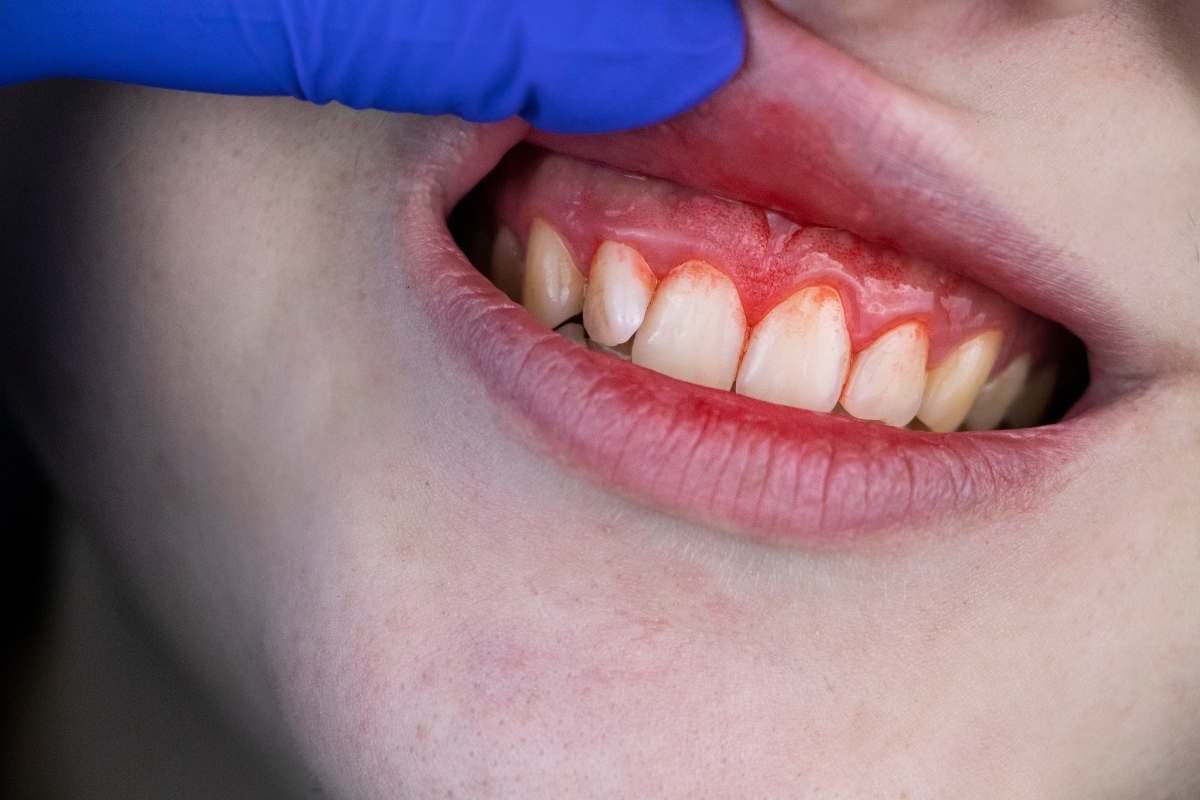

Пародонтальные заболевания часто развиваются скрытно, поэтому ранние симптомы могут легко остаться незамеченными. Чтобы сохранить здоровье десен, следует обращать внимание на следующие признаки. Ниже перечислены наиболее распространённые и важные симптомы пародонтальных заболеваний:

Кровоточивость десен

Отёк десен

Покраснение и чувствительность десен

Специалисты по пародонтологии учитывают эти симптомы для ранней диагностики. Благодаря пародонтологии можно остановить развитие заболевания и сохранить здоровье зубов. Раннее вмешательство помогает предотвратить эстетические и функциональные потери.